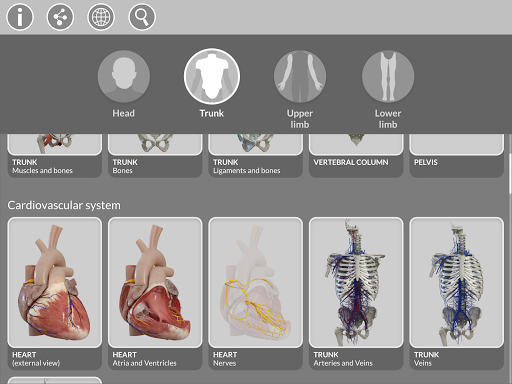

"Anatomía - Atlas 3D" permite estudiar la anatomía humana de forma fácil e interactiva.

La subdivisión por regiones y las vistas predefinidas facilitan la observación y el estudio de partes individuales o grupos de sistemas y las relaciones entre los diferentes órganos.

MODELOS ANATÓMICOS 3D

• Sistema musculoesquelético

• Sistema cardiovascular • Sistema

nervioso • Sistema respiratorio • Sistema digestivo • Sistema urogenital (masculino y femenino) • Sistema endocrino • Sistema linfático • Sistema ocular y auditivo CARACTERÍSTICAS • Interfaz sencilla e intuitiva • Rotar y hacer zoom en cada modelo en el espacio 3D • Opción para ocultar o aislar uno o varios modelos seleccionados • Filtro para ocultar o mostrar cada sistema • Función de búsqueda para encontrar fácilmente cada parte anatómica • Función de marcador para guardar vistas personalizadas • Rotación inteligente que mueve el centro de rotación automáticamente • Función de transparencia • Visualización de músculos a través de niveles de capas desde las superficiales hasta las más profundas • Al seleccionar un modelo o un pin, aparece el término anatómico relacionado • Descripción de los músculos: origen, inserción, inervación y acción • Mostrar/ocultar interfaz de usuario (muy útil con pantallas pequeñas) MULTILINGÜE • Los términos anatómicos y la interfaz de usuario están disponibles en 11 idiomas: latín, inglés, francés, alemán, italiano, portugués, turco, ruso, español, Chino, japonés y coreano • Los términos anatómicos se pueden mostrar en dos idiomas simultáneamente REQUISITOS DEL SISTEMA • Android 8.0 o posterior, dispositivos con al menos 3 GB de RAM Reversi

• Sistema cardiovascular

• Sistema nervioso

• Sistema respiratorio

• Sistema digestivo

• Sistema urogenital (masculino y femenino)

• Sistema endocrino

• Sistema linfático

• Sistema de ojos y oídos